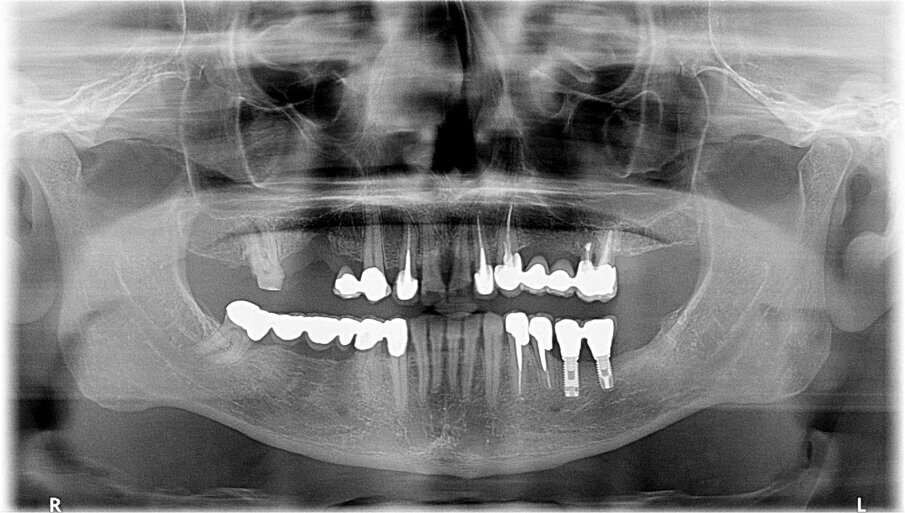

Il paziente di 50 anni in buono stato di salute, necessitava di una riabilitazione di tutta l’arcata superiore sia con impianti nei settori posteriori sia con corone sui denti frontali. Mentre nel sestante superiore destro era presente una quantità d’osso ideale per l’inserimento di impianti di diametro e lunghezza considerati standard, nel sestante sinistro era presente una quantità d’osso insufficiente sia verticalmente che orizzontalmente (Figg. 1-4). A causa dei timori del paziente sono stati esclusi interventi invasivi per incrementare i volumi ossei e si è deciso di inserire in posizione 24 un impianto BTI 3.0 3,3 x 10 mm e in posizione 26 un impianto BTI standard 3,7 x 5,5 mm con un minirialzo contestuale del seno mascellare.